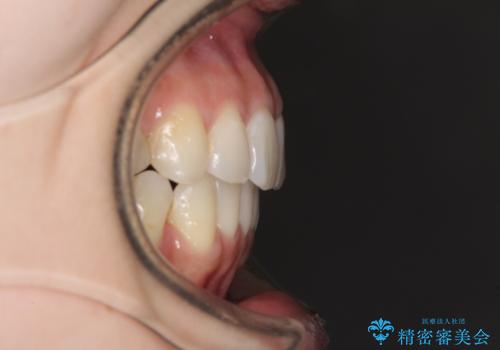

- 上下のデコボコと奥歯の咬みにくさを気にして来院された患者様です。

上顎骨の幅が下顎骨よりも小さいので、拡大装置により骨幅を広げて上下関係を改善し、その後インビザラインにて歯並びを整えることとしました。

上下の骨幅を改善したことで、スムーズに歯列矯正を行うことができました。

矯正治療中に近医で銀歯を外す治療を開始したため、治療後に奥歯の咬み合わせが不十分ですが(こちらは近医での治療により改善するとのこと)、歯列と咬み合わせが改善され、患者様には大変満足していただきました。